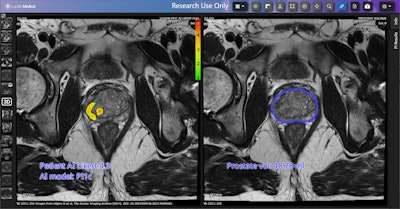

In collaboration with Lucida, LTHT is evaluating the effectiveness of the Prostate Intelligence (Pi) tool, an AI and machine-learning software system, for identifying prostate cancer lesions on MRI scans.

The ongoing study will compare AI-generated results from the Pi software against real-world outcomes for 100 patients who have recently completed a prostate cancer treatment pathway. The software highlights potential areas of concern on MRI scans and assesses risk scores and prostate size with AI algorithms that analyze prostate MR images. In clinical use, Pi would be set up to run automatically as soon as a patient’s MRI scan is completed.